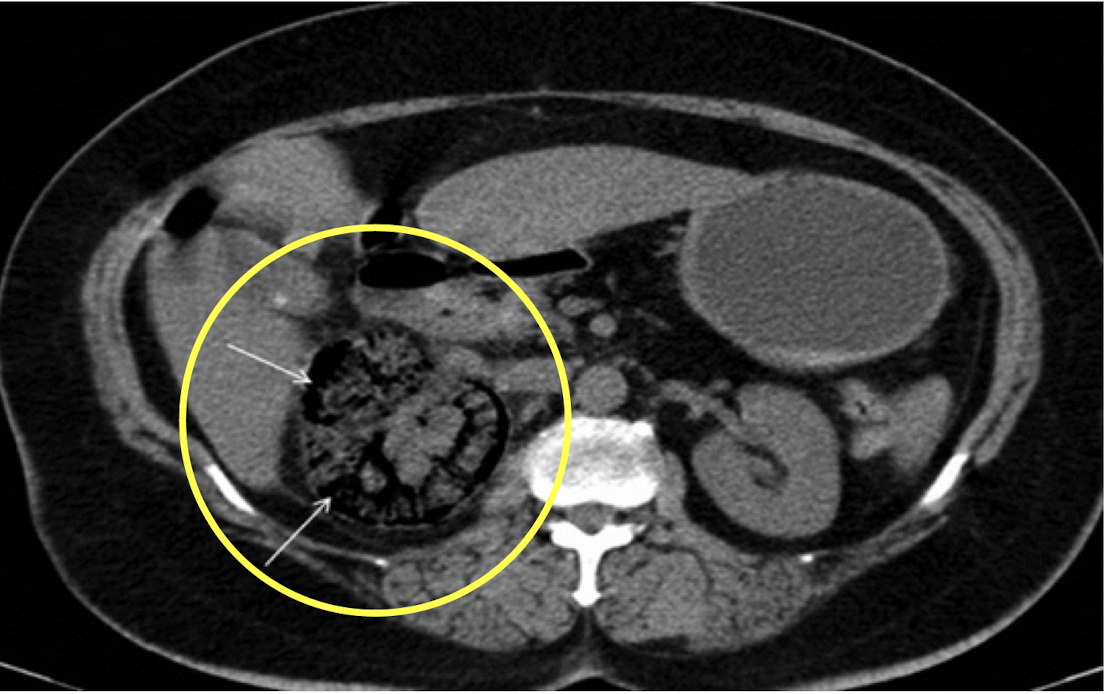

Trauma: Liver

CTA Abdomen/Pelvis IV contrast

Trauma: Spleen

CTA Abdomen/Pelvis IV contrast